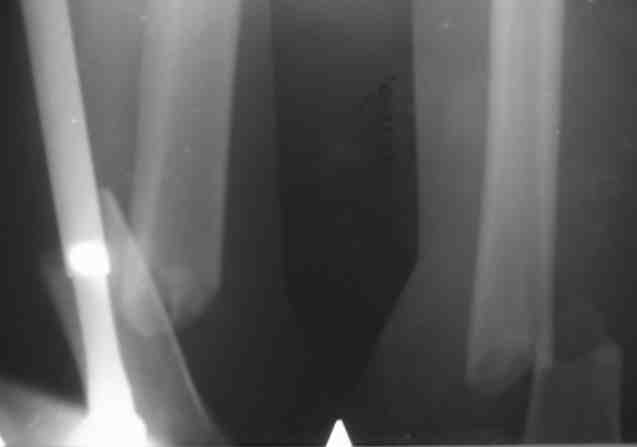

Поступил дядя 54 лет.Дорожная травма 14.10.2006

К нам попал на 11 сутки.Вроде как согласился на ретроградный штифт "Санатметал", но отказался!

Выполнили вот такой остеосинтез (вариант гаражной ортопедии - Александр Николаевич знает) модифицированным штифтом ЦИТО.

Есть сомнения в жесткости конструкции!

Обсуждается вопрос брейса-есть ли смысл?

P.S.Поллер винт внизу реально помог - сложность была (оперировали на 17 сутки)